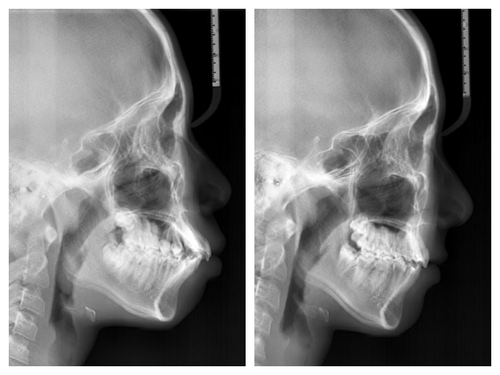

사실 골격적인 비대칭이 심해서 교정이 끝나도 비대칭이 남겠지만 돌출이 개선되면 훨씬 예뻐질것이기에 과감히 발치를 하고 좌,우 최대한 중심선을 맞추면서 교정을 끝낸 케이스

입이 들어가서 예뻐진 것 뿐아니라 사진을 찍으면 두드러지던 비대칭도 많이 줄어들었다.

네 개의 소구치를 발치하고 교정을 시작했다.

돌출입 교정을 통해 입술의 모습이 많이 바뀌니 잇몸 노출량도 훨씬 줄어서 웃을때 신경이 더 쓰인다고...